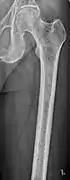

Femur with multiple myeloma lesions

The diagnostic examination of a person with suspected multiple myeloma typically includes a skeletal survey. This is a series of X-rays of the skull, axial skeleton, and proximal long bones. Myeloma activity sometimes appears as "lytic lesions" (with local disappearance of normal bone due to resorption). And on the skull X-ray as "punched-out lesions" (pepper-pot skull). Lesions may also be sclerotic, which is seen as radiodense.[47] Overall, the radiodensity of myeloma is between −30 and 120 Hounsfield units (HU).[48] Magnetic resonance imaging is more sensitive than simple X-rays in the detection of lytic lesions, and may supersede a skeletal survey, especially when vertebral disease is suspected. Occasionally, a CT scan is performed to measure the size of soft-tissue plasmacytomas. Bone scans are typically not of any additional value in the workup of people with myeloma (no new bone formation; lytic lesions not well visualized on bone scan).